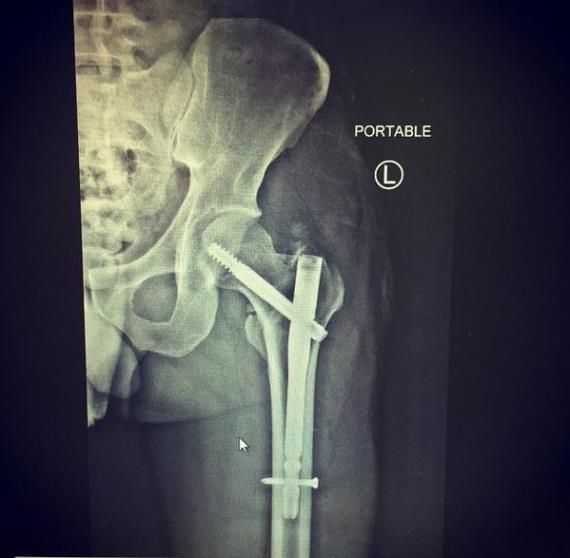

กลายเป็นเรื่องฮา!! หลังหนุ่ม ปอ ทฤษฏี ลงรูป IG อัพเดตอาการป่วยด้วยรูปฟิล์มเอกซเรย์ แต่เจ้ากรรม ชาวเน็ตกลับมุ่งความสนใจไปที่ ปอน้อย งานนี้เล่นเอาขำแตกกันถ้วนหน้าเลยที่เดียว หนุ่ม ปอ เผย ตอนนี้อาการดีขึ้นแล้ว อาทิตย์หน้าอาจได้ปลดไม้เท้าออก ไม่ซีเรียสกับเรื่องฟิล์มเอกซเรย์ ถือว่าเป็นของแถม แต่ไม่ได้มีเจตนา แค่อยากอัพเดทอาการเท่านั้นเอง

“อาการดีขึ้นมากแล้วครับผม จากฟิล์มเอกซเรย์ก็เห็นแล้วมันดีขึ้นเยอะ อาทิตย์หน้าไปพบคุณหมออีกทีอัพเดตอาการว่าจะปลดไม้เท้าออกซักอันหนึ่งออก”

“อาการปวด ไม่ปวดครับ แผลเล็ก จุดๆเอง สามที่ ไม่ได้มีกรีดฝั่งเหล็กครับ ฟื้นตัวเร็ว ต้องออกกำลังกาย ให้กล้ามเนื้อมันแข็งแรงครับ ตอนนี้ก็กายภาพบำบัดอยู่ที่บ้านครับ”

“เรื่องรูปฟิล์มเอกซเรย์ จริงๆผิดวัตถุประสงค์นะ ผมกับหมอและพยาบาลไม่มีใครเห็นเลย ให้ตายเถอะ(หัวเราะ) มันไม่ใช่อย่างที่ทุกคนคิดนะ มันไม่ใช่หรอกครับผม ไม่ซีเรียสหรอกครับ แค่อยากอัพเดตอาการให้ได้รู้กัน ก็ถือว่าเป็นของแถมนะ ตลกๆกัน ขำครับ คนทั้งโรงพยาบาลไม่มีใครคิดเลยนะ ตามเจตนาครับไม่ได้มุ่งหวังให้มันเป็นอย่างนั้น ผมก็ขำครับ”